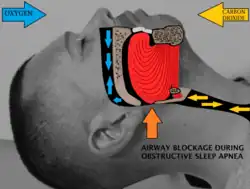

Sleep surgery is a range of surgical procedures to treat sleep-related breathing disorders (sleep-disordered breathing), especially obstructive sleep apnea (OSA). The spectrum of sleep-related breathing disorders also includes primary snoring (non apneic snoring), upper airway resistance syndrome, and obesity hypoventilation syndrome. These surgeries are performed by surgeons trained in otolaryngology, oral maxillofacial surgery, and craniofacial surgery.

Background

Obstructive sleep apnea (OSA) is defined as either cessation of breathing (apnea) for 10 seconds, or a decrease in normal breathing (hypopnea) with an associated desaturation in oxygen and arousal during sleep that lasts at least 10 seconds. In adults, it is typical to have up to 4.9 events per hour. In OSA, affected individuals are categorized based on how many apneas or hypopneas (apnea-hypopnea index or AHI) or events they have per hour.

Sleep surgery aims to reduce daytime sleepiness, increase quality of life, and improve parameters recorded on polysomnography.[2] In general, all the procedures achieve this by removing or preventing obstruction of the upper airway during sleep.